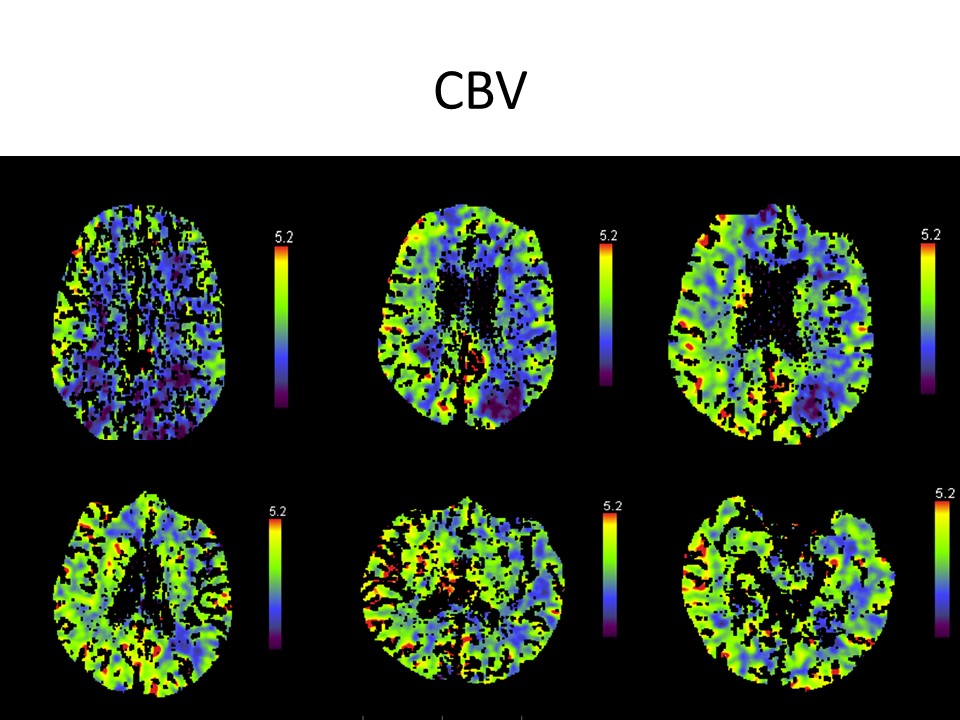

El estudio de la perfusión cerebral pone de manifiesto.

Un extenso territorio de retraso en mapas de tiempo a nivel de la totalidad del territorio de ambas carótidas con relativa área respetada a nivel de la circulación posterior.

Los mapas de volumen presentan algunas zonas parcheadas de menor perfusión.